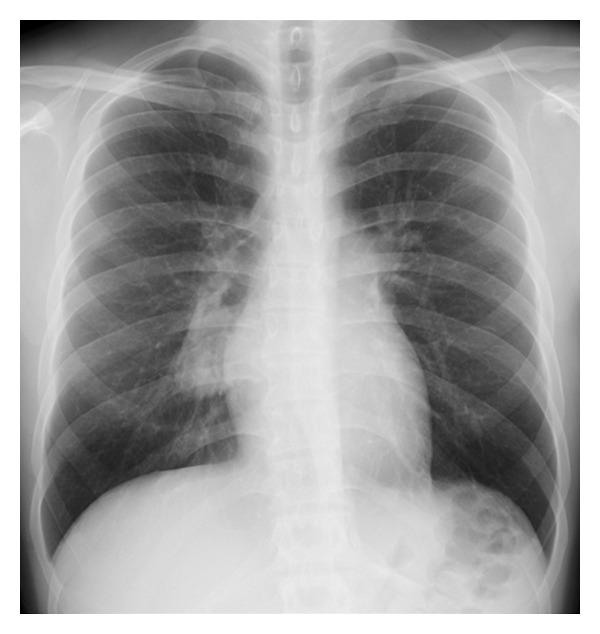

Castleman's disease is an uncommon lymphoproliferative disorder of unknown etiology, most often involving the mediastinum. It has 2 distinct clinical forms: unicentric and multicentric. Unicentric Castleman's disease arising from an intrapulmonary lymph node is rare, and establishing a preoperative diagnosis of this disease is very difficult mainly due to a lack of specific imaging features. We report a case of intrapulmonary unicentric Castleman's disease in an asymptomatic 19-year-old male patient who was accurately diagnosed by preoperative computed tomography (CT). The mass was incidentally found on a routine chest X-ray. A subsequent dynamic CT showed a well-defined, hypervascular, soft-tissue mass with small calcifications located in the perihilar area of the right lower lung. Three-dimensional CT (3D-CT) angiography indicated that the mass was receiving its blood supply through a vascular network at its surface that originated from 2 right bronchial arteries. The clinical history and CT findings were consistent with a diagnosis of unicentric Castleman's disease, and we safely and successfully removed the tumor via video-assisted thoracoscopic surgical lobectomy. This case shows that the imaging characteristics of these rare tumors on contrast-enhanced CT combined with 3D-CT angiography can be helpful in reliably establishing a correct preoperative diagnosis.

Castleman病是一种病因不明的罕见淋巴增生性疾病,最常累及纵隔。它有两种不同的临床形式:单中心型和多中心型。起源于肺内淋巴结的单中心型Castleman病很罕见,主要由于缺乏特异性影像学特征,术前诊断这种疾病非常困难。我们报告一例19岁无症状男性患者的肺内单中心型Castleman病,其通过术前计算机断层扫描(CT)被准确诊断。该肿块是在常规胸部X线检查时偶然发现的。随后的动态CT显示在右下肺门周围区域有一个边界清晰、血供丰富、有小钙化的软组织肿块。三维CT(3D-CT)血管造影显示该肿块通过其表面起源于2支右支气管动脉的血管网络获得血供。临床病史和CT表现与单中心型Castleman病的诊断相符,我们通过电视辅助胸腔镜手术肺叶切除术安全且成功地切除了肿瘤。该病例表明,这些罕见肿瘤在增强CT结合3D-CT血管造影上的影像学特征有助于可靠地建立正确的术前诊断。